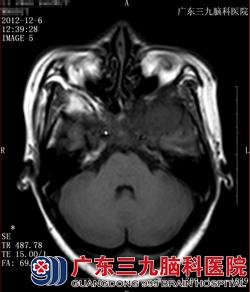

图一 图二

图一、图二:CT:颅底骨质呈骨性破坏,左侧中颅底示云雾状瘤骨。